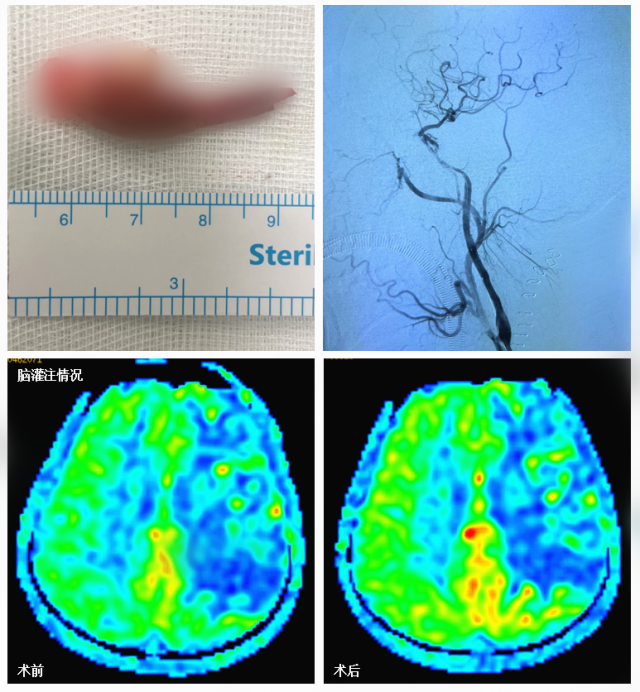

2018年头颈CTA示左侧颈内动脉起始部重度狭窄/2022年3月头颅MRI显示左侧颈内动脉供血区多发脑栓塞病灶,头颅MRA可见左侧颈内动脉全程闭塞,全脑血管造影可见左侧颈内动脉闭塞

郭毅与神外医师范玉龙配合,在显微镜下显露颈动脉分叉与颈内动脉起始部,小心切开动脉,清晰分辨出动脉壁各层与斑块,顺利将严重钙化的颈动脉斑块完整剥除。

在颈动脉切口处,由张小峰,神内主治医师王也、医师徐文灯与苏伟组成介入团队,继续开通剩余的闭塞段。由于斑块又长又硬,介入团队首先进行多次抽吸取栓,大部分斑块取出后,再通过球囊扩张拓宽血管管腔,植入支架,术中监测显示颅内血管完整显影,颈动脉血流最终恢复通畅。

神经外科医师完成颈动脉内膜剥脱,后介入团队继续开通剩余血管,复查造影颈内动脉血流恢复通畅,术后复查头颅影像学提示左侧大脑半球灌注比术前改善

术后,患者不仅没有出现头痛、恶心、呕吐等症状,也没有发生相关并发症,复查显示,患者左侧大脑半球血流比术前有了明显改善。一周后,患者顺利出院。